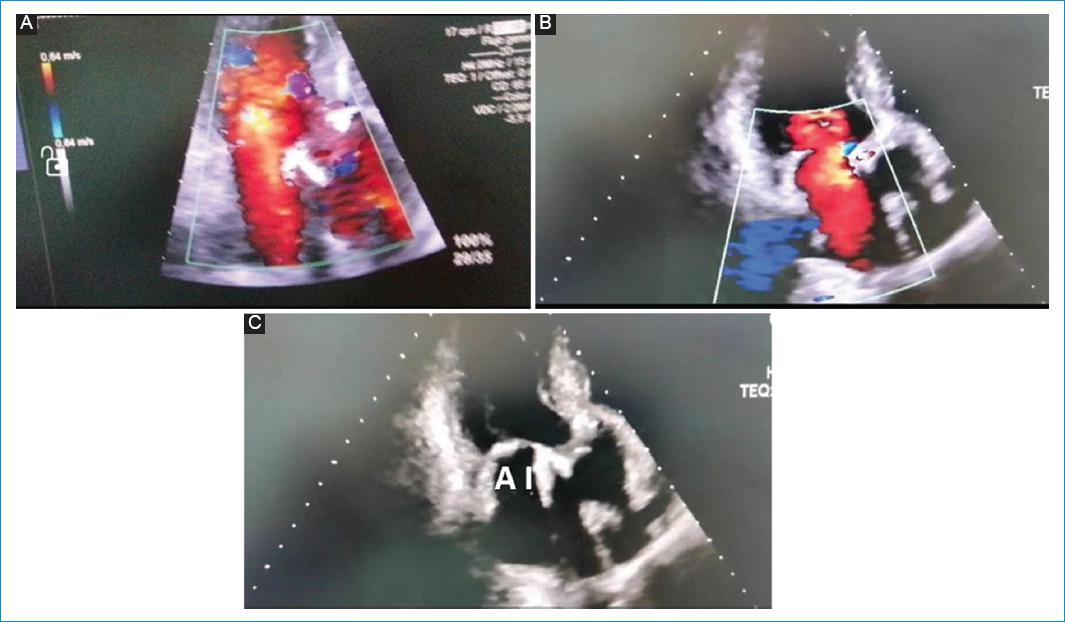

Tres días después tuvo mejoría clínica notoria en cuanto a parámetros hemodinámicos y ecocardiográficos, por lo cual se decidió cierre del mediastino (no se encontraron signos de compresión mecánica auriculoventricular, índices cardíacos adecuados) (Figs. 6 y 7).

Figura 6 Ecocardiografía transtorácica, posquirúrgico # 3 (día 3) – Tórax abierto. Ventana ecocardiográfica apical 3 cámaras. A: se observa flujo venoso amplio a través de la aurícula izquierda ya expandida y se visualiza el flujo venoso de las venas pumonares derechas e izquierdas (B). C: aurícula izquierda sin compresión extrínseca y bioprótesis aórtica.

Figura 7 Ecocardiografía transtorácica, posquirúrgico # 3 (día 3) – Tórax abierto. A: flujo normal por doppler color a través de la aurícula izquierda en ventana transtorácica apical 5 cámaras. B: aurícula izquierda ya sin compresión con su tamaño normal. C: imagen transtorácica apical 5 cámaras en la que se observan ambas aurículas expandidas normalmente y la bioprótesis aórtica en el centro. AD: aurícula derecha; BA: bioprótesis aórtica.

Al siguiente día se retiró soporte inotrópico y vasopresor. Posteriormente se trasladó a hospitalización, donde se realizó compensación de sus enfermedades de base. Evolucionó de forma adecuada (Figs. 8 y 9).

Figura 8 Ecocardiografía transesofágica, posquirúrgico # 3 (día 6) – Cierre definitivo del tórax. Ventanas medioesofágicas a 0° visualizando la aurícula izquierda expandida completamente en la parte superior de las imágenes, A: 4 cámaras y B: 5 cámaras, en esta se observa la bioprótesis aórtica. C: aurícula izquierda en mayor aumento para resaltar su tamaño y la ausencia de compresión de sus paredes.

Figura 9 Ecocardiografía transtorácica, posquirúrgico # 3 (día 6) – Cierre definitivo del tórax. Ecocardiograma transesofágico, ventana medioesofágica - 29°. Se observan el ventrículo izquierdo (VI), la aurícula izquierda (AI), la orejuela de la aurícula izquierda (OAI) y la vena pulmonar superior izquierda (VPSI). Se observa la aurícula izquierda totalmente expandida y la vena pulmonar superior izquierda con flujo normal y sin compresión extrínseca.